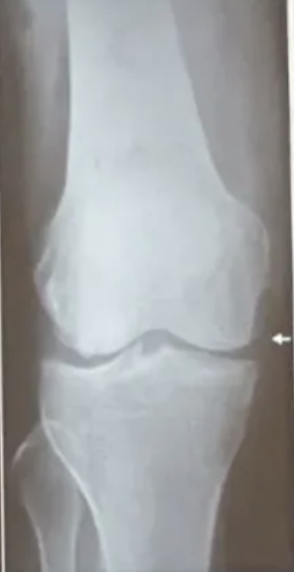

Rx se puede observar

A

• Engrosamiento y esclerosis de la lámina subcondral

• Osteofitos en borde articular

• Distensión de cápsula articular

• Cambios en tejido blando periarticular

Rodillas

• Deformidad → genu varo

• Quistes subcondrales

• Erosiones centrales

• Meseta tibial

osteofitos

Clasificación rx artrosis donde hay ausencia de osteofitos, estrechamiento o quistes

Clasificación rx artrosis donde solo hay osteófitos y dudoso pinzamiento de espacio articular

Grado 1 = dudoso